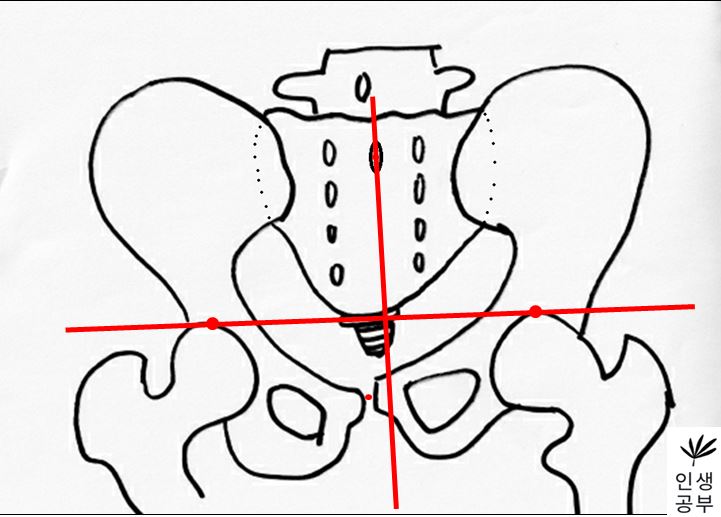

6) 1번째나 2번째 엉치뼈 결절(sacral tubercle) 정가운데 찍은 점에서 대퇴골두선(FHL : Femur Head Line)을 기준으로 수직인 선을 긋습니다.

선을 그었을 때 점이 있는 쪽 골반이 IN이 됐다는 뜻이고, 없는 쪽은 EX 되었다는 뜻입니다.